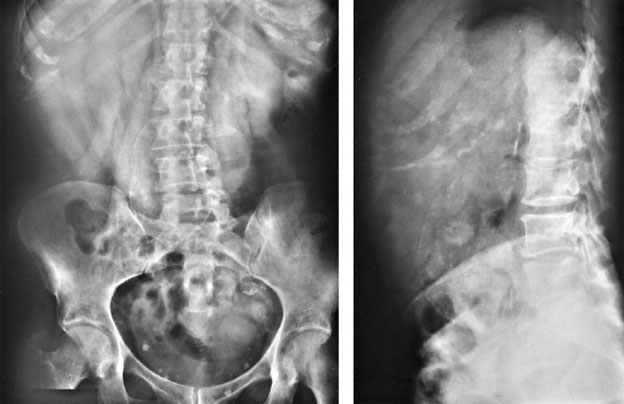

A 78-year-old woman is brought to the emergency department by ambulance because of a 6-hour history of severe, progressive back pain that radiates to her abdomen. She rates the pain as a 7 on a 10-point scale. She called an ambulance because she was too weak to walk. She reports no recent trauma. Medical history is remarkable for hypertension and breast cancer. Her only medication is atenolol. She is 173 cm (5 ft 8 in) tall and weighs 100 kg (220 lb); BMI is 34 kg/m2. Vital signs are temperature 37.0°C (98.6°F), pulse 122/min, respirations 26/min, and blood pressure 142/96 mm Hg. Chest is clear to auscultation. Abdomen is soft with hypoactive bowel sounds. There is mild palpable paraspinous tenderness in the lumbar region. Neurologic examination shows no abnormalities. X-rays of the lumbar spine are shown. Which of the following is the most appropriate next step?